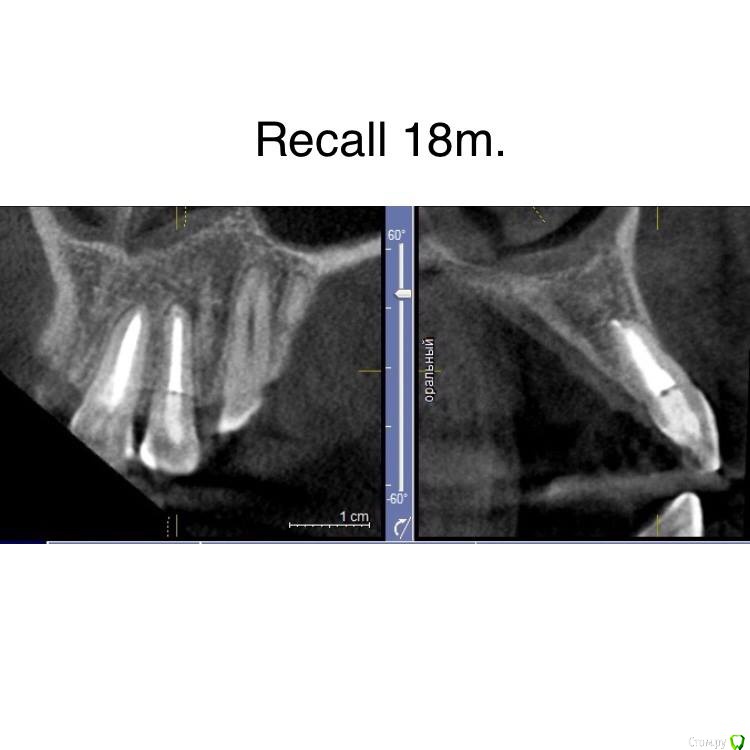

Гарриевич Опубликовано 2 октября, 2018 Автор Поделиться Опубликовано 2 октября, 2018 пришло время отчета 5 Ссылка на комментарий